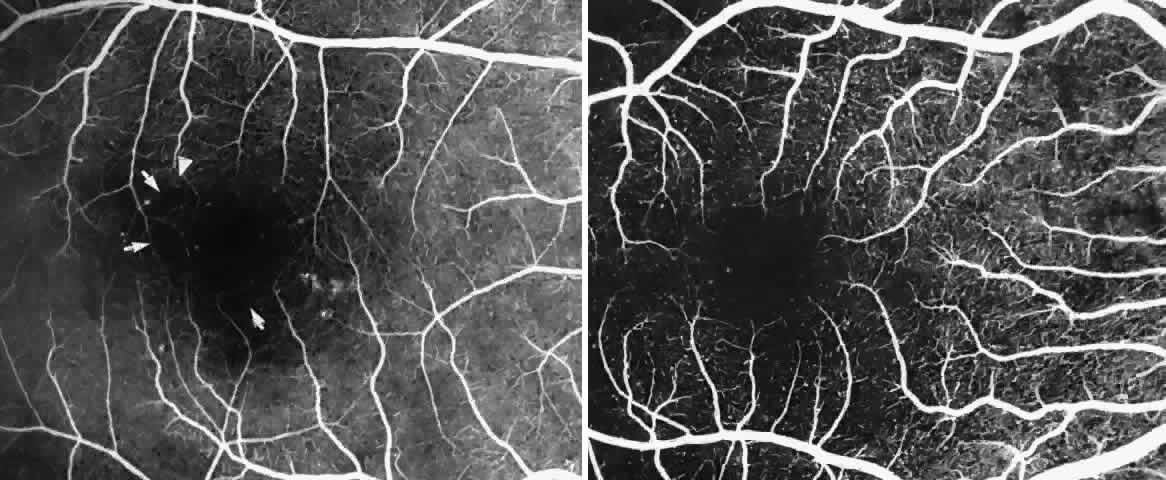

Other macular and perimacular changes include microaneurysm-like dots, dark and enlarged segments of arterioles, hairpin-shaped venular loops, pathologic avascular zones, and widening and irregularities of the foveal avascular zone (Figs. 11 and 12). In the Jamaican cohort study evaluating children with homozygous sickle cell anemia and SC disease between the ages of 5.0 and 7.5 years of age, no pathologic avascular zones could be identified despite a high incidence of peripheral vascular closure.31 In evaluating patients with homozygous sickle cell anemia, no relationship between ISC counts and macular abnormalities or visual acuity could be found.101 Using fluorescein angiography, investigators have found the foveal avascular zone to be significantly larger in eyes with clinical evidence of sickle cell maculopathy as compared with normal eyes and eyes without clinical evidence of sickle cell maculopathy.102–104

Careful examination by fluorescein angiography, looking for areas of capillary dropout and other capillary abnormalities, is often necessary to identify the macular changes. These changes may be transient, and the macula may appear normal on subsequent fluorescein angiograms (Fig. 13). Although fluorescein angiography may or may not demonstrate reperfusion of a previously occluded capillary bed, a loss of the inner retinal layers results in an ophthalmoscopic focal concavity with an abnormal reflex (retinal depression sign) (see Fig. 8E).105,106 These changes are usually permanent. The retinal depression sign is not pathognomonic of sickle cell disease and may be seen with other arteriolar occlusive diseases, such as embolic retinopathy, vasculitis, and hypertension.

Macular Function Testing in Sickle

Cell MaculopathyThe visual acuity in patients with sickle cell disease is often normal, despite the presence of an enlarged foveal avascular zone or other evidence of sickle cell maculopathy (Fig. 14). In addition, patients with sickle cell maculopathy have a remarkable absence of visual complaints. Although 55% of patients with homozygous sickle cell anemia had abnormal contrast sensitivity, no significant relationship was demonstrated between contrast sensitivity and macular vascular abnormalities.101 Automated visual field analysis has demonstrated significantly larger scotomas in patients with abnormally enlarged foveal avascular zone.102 Color vision testing has revealed a greater incidence of blue-yellow defects in patients with sickle cell retinopathy; however, no significant correlation has been demonstrated between color vision defects and the presence of sickle cell maculopathy.98,107